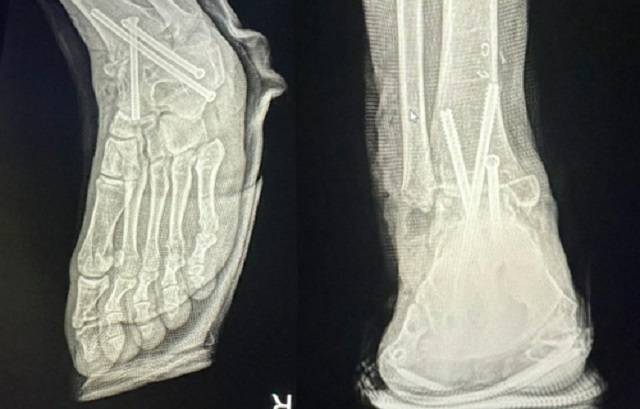

복숭아뼈 자르고 긴 철심 3개 박아놔

16일 연합뉴스에 따르면 직장인 A(29)씨는 지난 3월10일 왼쪽 발목이 안쪽으로 접혀 바닥을 제대로 디딜 수 없는 문제를 해결하기 위해 서울의 B 병원에서 수술받았다. 그러나 그가 2시간여의 수술이 끝난 후 마취에서 깨어나 보니 멀쩡하던 오른발 복숭아뼈가 잘리고 철심 3개가 박혀있었다고 한다. A씨는 즉시 경찰에 신고해 의료과실 증거를 확보하고 다시 왼발 수술을 받았다.